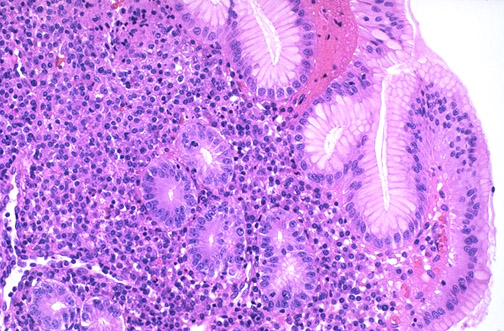

Image 8.2

The high power microscopic appearance of the gastric mucosa is seen here. The inflammatory cell infiltrates are composed of lymphocytes and plasma cells (occasionally, some neutrophils could be present as well).